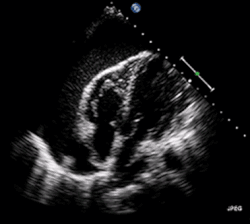

A 2D echo transthoracic echocardiogram of pericardial effusion. The "swinging" heart. | |

ECG: may present with sinus tachycardia, low voltage QRS as well as electrical alternans.[2] Due to the fluid accumulation around the heart, the heart is further away from the chest leads, which leads to the low voltage QRS. Electrical alternans signifies the up-and-down change of the QRS amplitude with every beat due to the heart swinging in the fluid (as displayed in the ultrasound image in the introduction) .[1] These three findings together should raise suspicion for impending hemodynamic instability associated with cardiac tamponade.

Echocardiogram (ultrasound): when pericardial effusion is suspected, echocardiography usually confirms the diagnosis and allows assessment of the size, location and signs of hemodynamic instability.[4] A transthoracic echocardiogram (TTE) is usually sufficient to evaluate pericardial effusion and it may also help distinguish pericardial effusion from pleural effusion and MI. Most pericardial effusions appear as an anechoic area (black or without an echo) between the visceral and the parietal membrane.[1] Complex or malignant effusions are more heterogeneous in appearance, meaning they may have variations in echo on ultrasound.[5] TTE can also differentiate pericardial effusion based on the size. Although it's difficult to define size classifications because they vary with institutions, most commonly they are as follows: small <10, moderate 10–20, large >20.[5] An echocardiogram is urgently needed for evaluation when there is concern for hemodynamic compromise, a rapidly developing effusion or history of recent cardiac surgery/procedures.[1]

A large anechoic (black) pericardial effusion as seen on ultrasound. Closed arrow: the heart, open arrow: the effusion